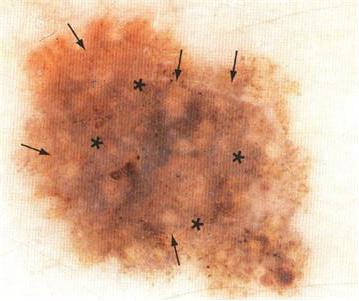

皮肤镜下,医生看出的蛛丝马迹:不对称,蓝白结构

这似乎是一个正常的痣,但我们通过皮肤镜发现确是这样的:不对称,可见蓝-白结构,高度怀疑黑素瘤(恶性肿瘤,皮肤肿瘤中死亡率最高的),可能大家对黑素瘤不是很清楚,但说到非诚勿扰中的孙红雷脚上的“痣”就明白了。这种肿瘤一定要早发现早治疗。